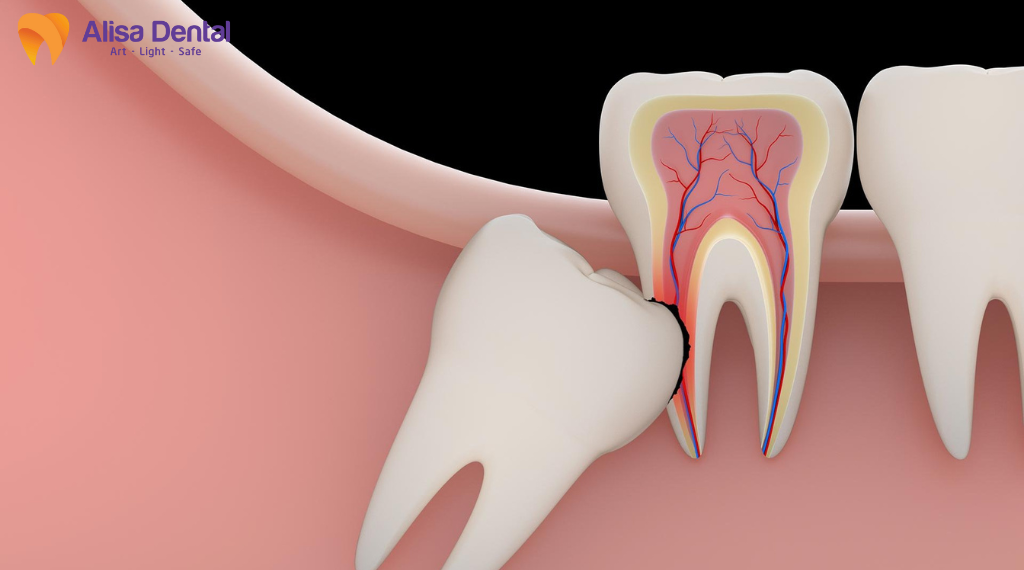

Đặc điểm mọc lệch, mọc ngầm của răng khôn

Răng khôn thường nằm sâu trong xương hàm, mọc lệch hoặc chèn ép răng kế cận, khiến quá trình nhổ phức tạp hơn so với răng thông thường. Việc phải bóc tách mô rộng, can thiệp vào xương hoặc chia nhỏ thân răng làm vùng tổn thương lớn hơn, kéo dài thời gian lành thương. Đây là yếu tố nền khiến nguy cơ viêm, sưng kéo dài hoặc khó hồi phục cao hơn, ngay cả khi quy trình được thực hiện đúng.